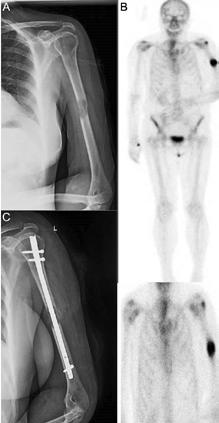

Figura 1: Cazul unei femei de 66 de ani, cu probleme de sănătate complexe, care a suferit o fractură patologică la nivelul humerusului din cauza unei metastaze. (A) Evidențiază metastaza osteolitică din humerus. (B) Imagine scintigrafică ce arată răspândirea sistemică. (C) Imagine postoperatorie care prezintă o tijă centromedulară utilizată pentru osteosinteză, permițând mișcarea imediată a brațului.

Figura 2 - Bărbat de 59 de ani, fără antecedente medicale semnificative și fără spitalizări anterioare. Pacientul a ajuns la urgențe cu durere bruscă și mobilitate redusă a șoldului drept, apărute în timp ce încerca să prindă un mijloc de transport în comun. Radiografia a arătat o fractură patologică la nivelul femurului drept (A). Investigațiile suplimentare, inclusiv analize de laborator și CT toraco-abdominopelvin, au relevat o tumoră canceroasă la rinichiul stâng. Deoarece metastaza era limitată la treimea superioară a femurului drept, s-a decis îndepărtarea chirurgicală a leziunii renale și reconstrucția femurului cu o proteză modulară (B).

Figura 3: Bărbat de 69 de ani cu metastaze avansate la nivelul femurului proximal și sacrumului. Imaginea arată osteoliză semnificativă, indicând riscul iminent de fractură patologică. (A) Prezintă o tu-

moră osteolitică în femur, iar B și C arată scanări CT care evidențiază extinderea metastazelor în femur și sacrum. Scintigrafia osoasă (D) oferă dovezi suplimentare ale răspândirii extinse a bolii. Din cauza prezenței unei tumori inoperabile, pacientul a urmat un plan de tratament pentru ameliorarea simptomelor și îmbunătățirea calității vieții, care a inclus radioterapie și ablație cu radiofrecvență pentru reducerea durerii și stabilizarea osului.